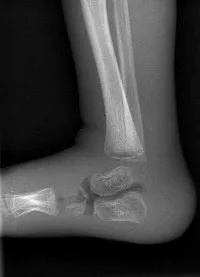

Adam Jones, a clinical scientist in radiation safety, has worked out how to get better quality X-ray images of babies’ ankles, using existing equipment and without increasing the radiation dose.

Adam tried setting up the equipment in different ways and took images of a ‘phantom’ baby’s foot, a model that trainee radiographers practice on.

The Evelina London radiologists and radiographers reviewed the results and agreed that one particular set up had significantly improved the image quality.